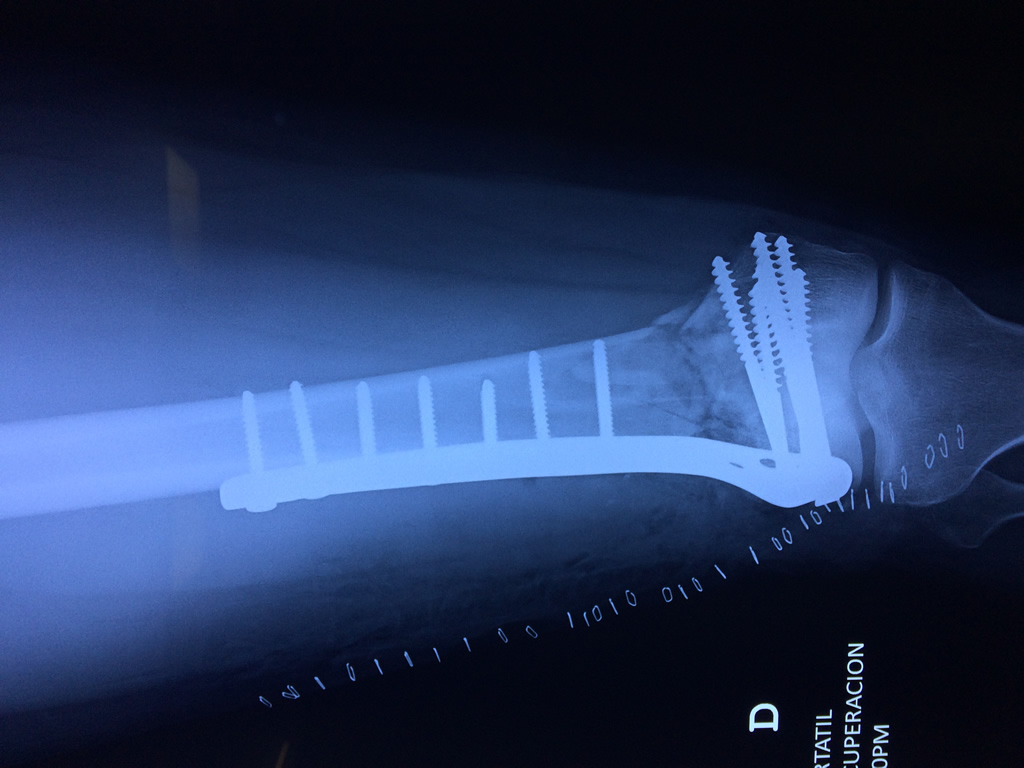

Cirugías de Codos - Fémur

El fémur es el hueso del muslo, el segundo segmento del miembro inferior. Es el hueso más largo, fuerte y voluminoso del cuerpo humano.